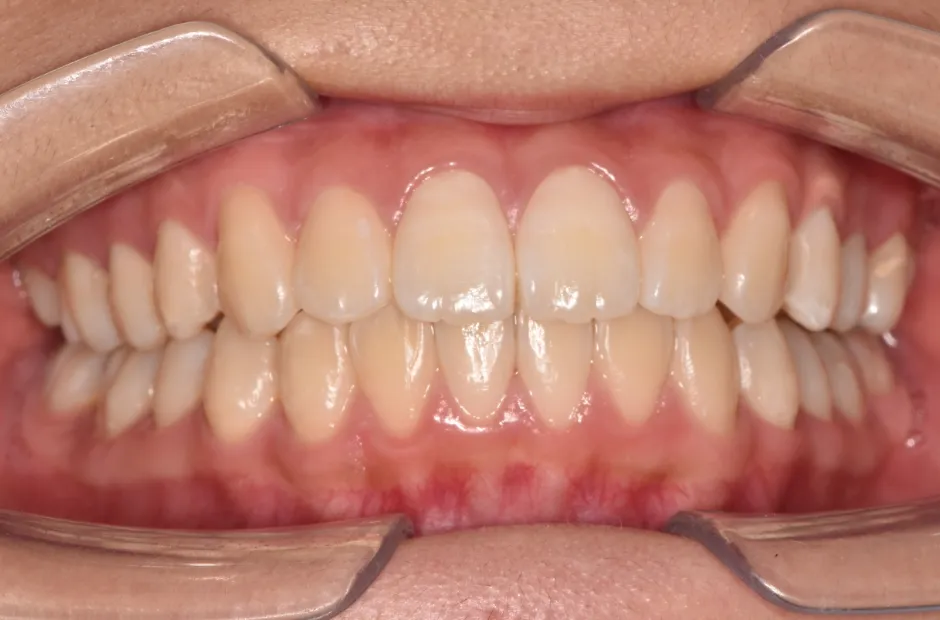

治療症例

ブラケット矯正

前歯部反対咬合

| 診断名・主訴 | 前歯部反対咬合 |

|---|---|

| 年齢・性別 | 14歳・男性 |

| 治療期間・回数 | 1年2か月 |

| 治療に用いた主な装置 | ブラケット矯正 |

| 抜歯部位 | なし |

| 治療費 | 60万円(税抜) |

| リスク・副作用 | 装置による違和感・疼痛・歯肉退縮・歯根吸収・虫歯のリスクなど |

治療前

治療後